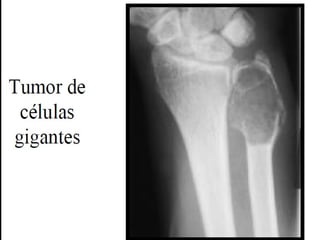

Tumor de células gigantes

• Se denomina así por que está constituido por

células multinucleadas gigantes de tipo osteoclasto

(osteoclastoma)

• Es un tumor infrecuente relativamente benigno

pero localmente agresivo.

• Suele aparecer entre la tercera y quinta década.

• Afectan a las epífisis y metáfisis sobre todo en la

rodilla.

• La mayoría son solitarios pero pueden ser múltiples.

Tumor de células

gigantes

- Tumores grandes y de color pardo rojizo que

sufren frecuentemente degeneración quística.

- Están formados por células mononucledas

ovaladas uniformes con membranas celulares

mal definidas, mitosis frecuentes y que parecen

crecer en un sincitio.

- En forma dispersa se observan numerosas

células gigantes de tipo osteoclasto (100 o más

núcleos).